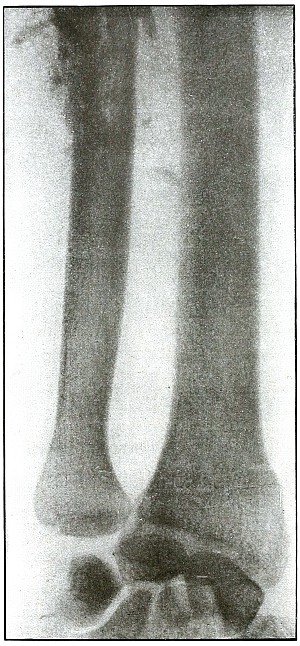

Gunshot fracture, tibia and fibula |

130 |

| 61. |

Gunshot fracture, tibia and fibula |